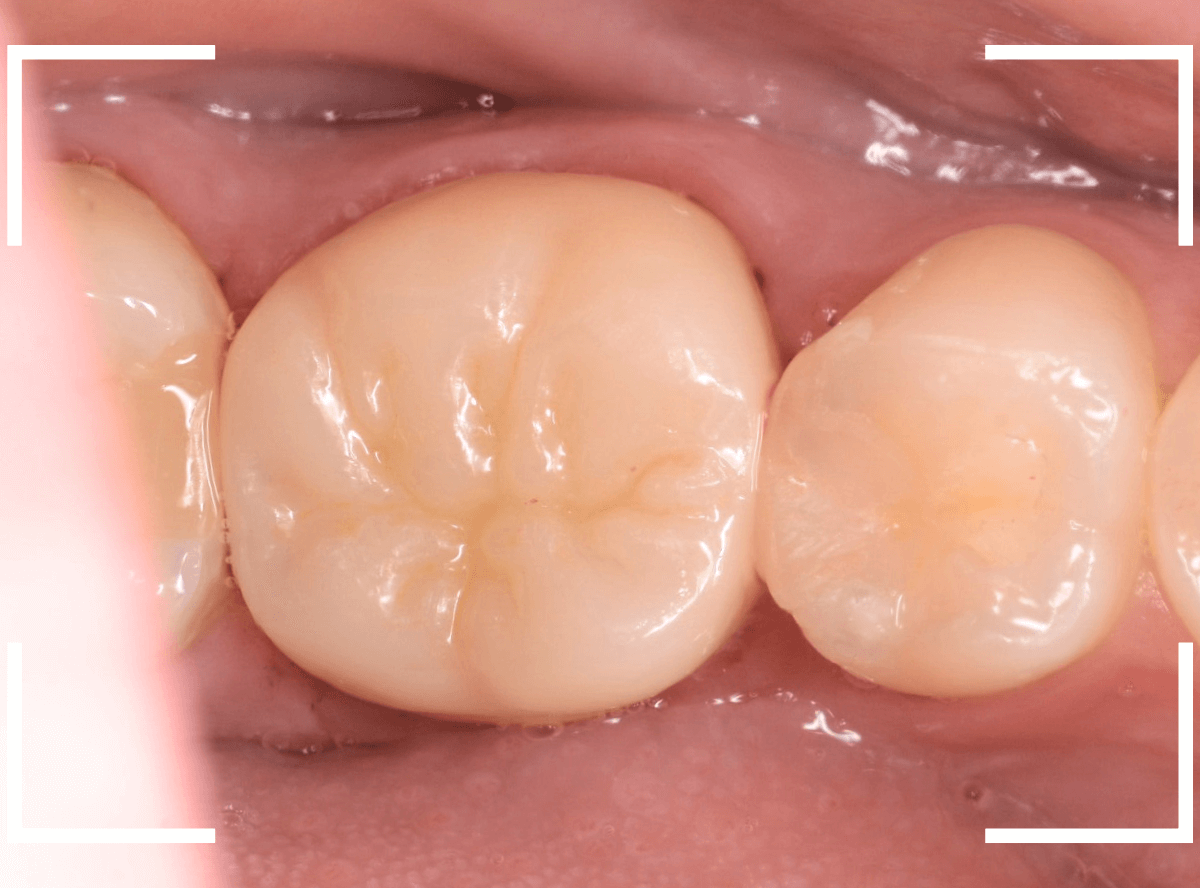

仮歯でしばらく経過観察し、症状がないのを確認した後に、型どりをして(オール)ジルコニア・クラウンを製作しました。

お口の中でジルコニアに置き換えた後も、特に症状なく経過されているようで、ホッとしました。